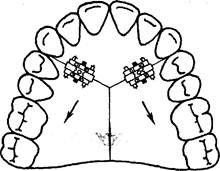

В случае вестибулярного положения клыка, причиной которого явилось мезиальное перемещение боковых зубов, можно изготовить ортодонтический аппарат для их дистального перемещения (рис. 13.40).

При двустороннем мезиальном перемещении боковой группы зубов изготавливают пластинку с двумя винтами и тремя секторальными распилами (рис. 13.41). В этом случае жевательные зубы перемещают-

Рис. 13.39. Пластинка на верхнюю челюсть с секторальным распилом для перемещения верхних фронтальных зубов в губном направлении.

ся дистально, а передние — в губном направлении.

Рис. 13.40. Пластинка на верхнюю челюсть с секторальным распилом для дистального перемещения верхних боковых зубов.

Рис. 13.41. Пластинка на верхнюю челюсть с двумя винтами и тремя секторальными распилами.